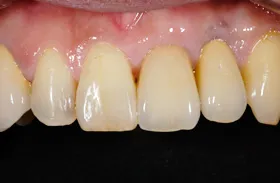

前歯欠損の為来院されたケース

■治療前

■治療後

治療のポイント

- 骨幅が狭い状態です。

- インプラントを埋めると同時に、骨を作る処置をさせて頂きました。

| 主訴 | 上顎の抜歯した箇所の機能障害・審美障害 |

|---|---|

| 治療方法 | 上顎の欠損部位に1本のインプラントを埋入し、同時に外科的治療で骨造成を行った |

| 治療期間 | 約1年 |

| 通院回数等 | 10回 |

| 費用 | 550,000円(税込) |

| リスク・副作用 | 外科的に骨を作る為、治療後に腫れることがある |